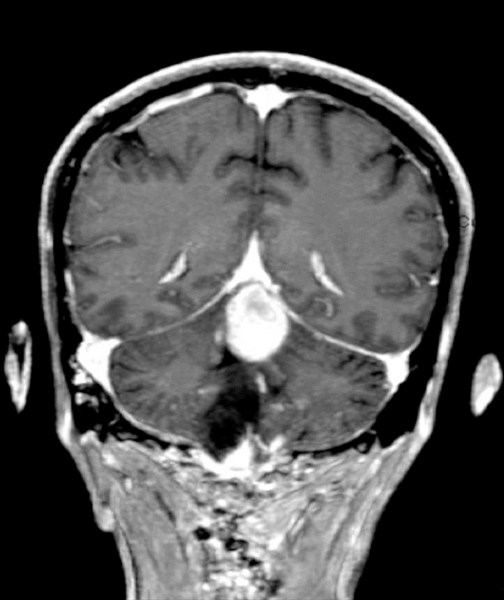

Ο έλεγχος με μαγνητική τομογραφία ανέδειξε ευμεγέθες αιμαγγειοβλάστωμα υποσκηνιδιακά με πίεση επί της 4ης κοιλίας καθώς και μια μικρότερη βλάβη στο στέλεχος συνοδευόμενη από κυστικό τμήμα με έντονα πιεστικά φαινόμενα.

Προεγχειρητική μαγνητική τομογραφία που απεικονίζει το ευμεγέθες αιμαγγειοβλάστωμα υποσκηνιδιακά και τα 2 μικρότερα στην περιοχή του στελέχους.